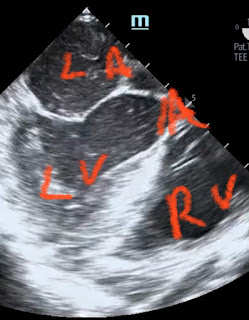

Было выполнено чреспищеводное эхо:

Подсказка к видео (LA= ЛП; LV= ЛЖ; RA= ПП;RV=ПЖ):